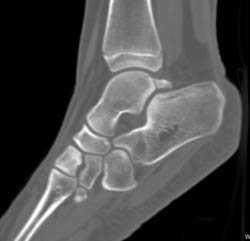

Diagnosis

Surgical Fusion